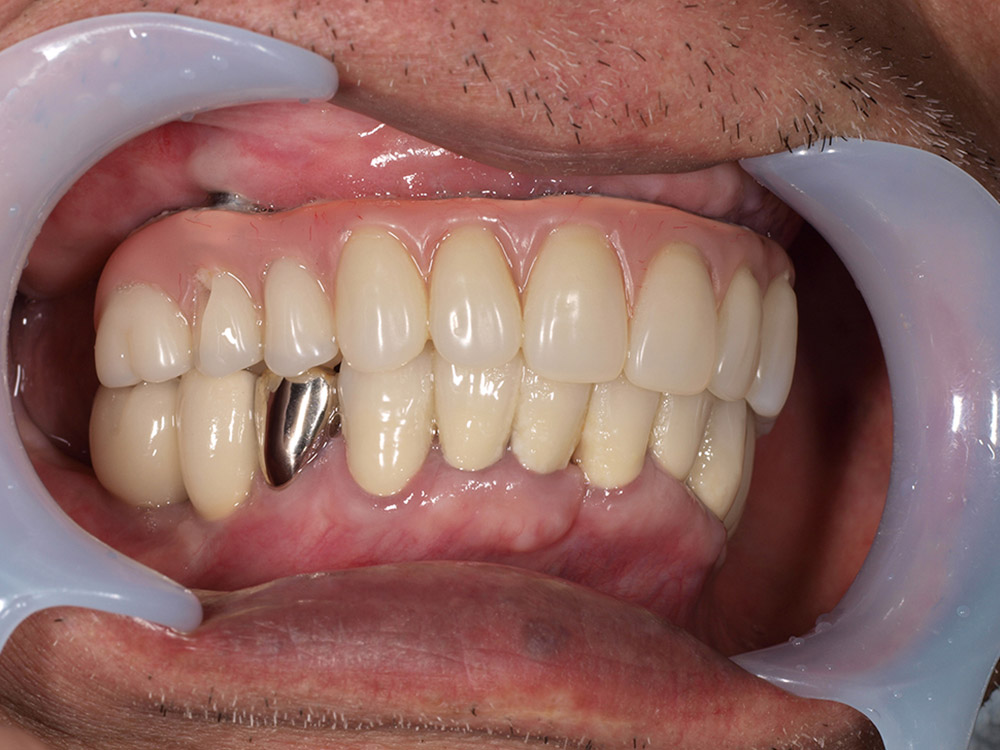

上部構造(人工歯)の装着

インプラントと骨が結合し、口腔内が安定した後、最終的な上部構造を装着します。オールオン4の上部構造は、前歯から奥歯まで連結したブリッジ状の人工歯で、失われた歯茎の部分も人工材料で一体的に作られています。全て一体で作られた人工歯は、歯の大きさ、歯並び、歯茎の引き締まり具合も全て左右対称に理想的な状態にデザインされており、優れた審美性を提供します。唇の張りまで回復するため、清潔で若々しい印象を目指すことができます。